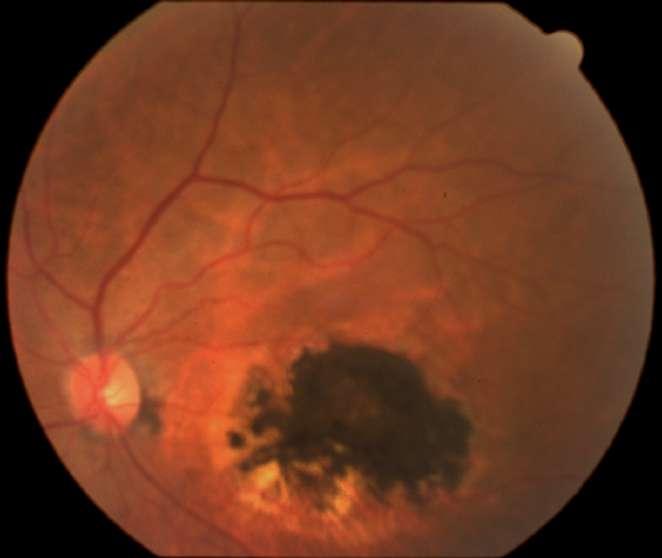

3.A. MELANOMA COROIDEO

Caso aportado por Dra. María José Vergara

Aü Fondo de ojo OD (Imagen A, B y C): Lesión pigmentada localizada a nasal a nivel coroideo, cuyas mediciones son de aprox 10x4mm en sus ejes cefalocaudaltransversal respectivamente

ü Mujer 70 años refiere cuadro de 1 mes de evolución caracterizado por fotopsias y entopsias en ojo derecho con AV conservada.

B C

Imagen D y E

ü Desprendimiento de vitreo posterior

ü Desprendimiento de retina focal inferior exudativa

ü Se constata lesion nasal 3hrs, forma de cupula cuyos diámetros máximos son:

-Al corte longitudinal: Base: 10.85nm, altura 2.58nm

-Al corte transversal: Base 8.81nm; altura 3.64nm con elementos de vascularidad

Dü El melanoma coroideo es el tumor primario intraocular más frecuente en el adulto

ü La mayoría puede diagnosticarse por sus signos clínicos, sin embargo existe un porcentaje de melanomas que requieren ecografías para diferenciarlos de otras lesiones pigmentadas

ü Para conseguir diferenciar con seguridad que estamos frente a un melanoma, el tumor debe superar los 2-2.5mm de grosor

ü Su morfología puede variar, siendo cupuliforme (la forma más frecuente) o presentando creciemiento <<en champiñon>> (forma carácterística, especialmente en tumores de gran tamaño, debido a la ruptura de membrana de Bruch). Menos frecuentemente puede ser binodular, multinodular o difuso

ü Es un tumor de celularidad densa, lo que se traduce en una ecogenicidad media– baja, estructura interna homogénea y gran atenuación. Es por ello que se aprecia el denominado ángulo kappa en el modo A, en el que aparece un primer piso alto correspondiente a la retina con una disminución marcada de los ecos posteriores y sombra posterior en eco B.

ü Característicamente presenta un alto flujo vascular en la base, por lo que aparecen <<flickering spikes>>. También es típica la excavación coroidea expresada como una baja ecogenicidad en la base del tumor

ü La ecografía es una técnica que también nos permite valorar, con una gran sensibilidad, la extensión extraescleral de un melanoma uveal. Para que esta pueda ser detectada debe ser igual o superior a 1.5mm, apreciándose un área vacío ecogénico bien delimitado, homogéneo, adyacente a la masa intraocular

ü La ecografía también nos permite valorar la presencia de un desprendimiento de retina seroso que habitualmente se extiende desde el margen tumoral hacia la zona ocular inferior

Clement F . “Angiografía”. Diagnóstico por la imagen en la retina, Sociedad Española de Retina y Vítreo, editado por Ignasi Jügens, Elservier, 2014, pp 41-66 E